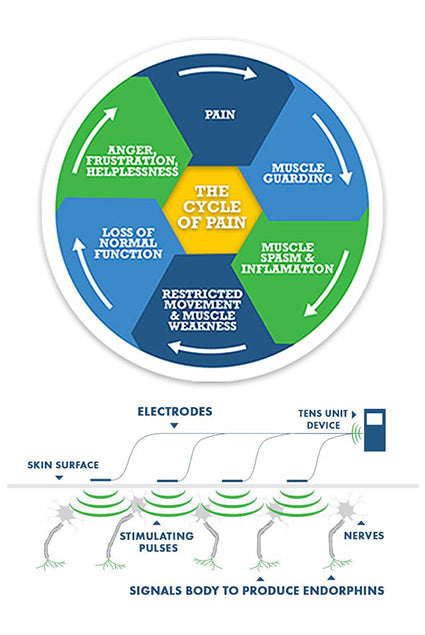

TENS stands for (Transcutaneous Electrical Nerve Stimulation). TENS therapy units are predominately used for nerve related pain conditions (acute and chronic conditions). TENS machines work by sending stimulating pulses across the surface of the skin and along the nerve strands.

The stimulating pulses help prevent pain signals from reaching the brain. TENS devices also help stimulate your body to produce higher levels of its own natural painkillers, called "Endorphins".